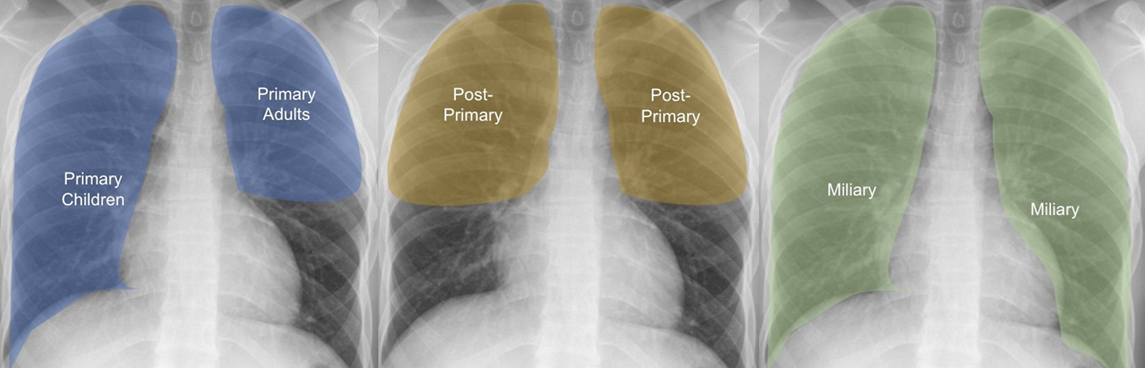

COVID-19 on Chest CT and X-ray

Our COVID-19 content is for healthcare professionals wishing to accurately diagnose COVID-19 on chest X-ray and CT scans. It trains users to identify the presence and severity of the infection, and to differentiate these from other conditions that may present in a similar manner.